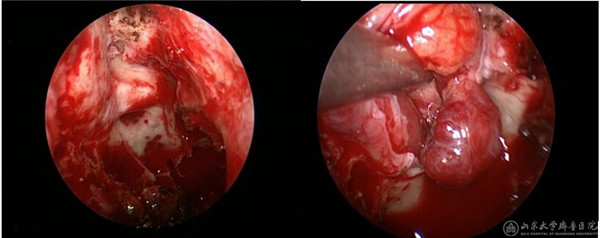

患者中年男性,3个月前无明显诱因出现右眼视物模糊伴视野受限。在多家绿帽社就诊,确认为右眼眶内肿瘤,病变位于右侧眶尖部,压迫视神经,手术风险较大。患者及家属仔细考虑后来我院就诊。徐淑军教授及陈腾教授经过反复观察患者眼眶磁共振及CT后,鉴于病变位于右侧眶尖部内上象限,决定对该患者进行神经内镜下经鼻蝶入路的眼眶手术。该手术尚未在我院独立完成过,手术涉及眼科、耳鼻喉科、神经科等多个学科的解剖及临床知识,难度较大,风险较高。徐淑军教授结合神经导航系统,将患者的影像学资料汇总入神经导航软件,模拟出手术的路径和术中需要注意避免损伤的重要血管及神经。决定采取神经内镜下眶内肿瘤切除术,并在功能内镜组成员李超副主任医师、杨宁主治医师协助下完成。手术过程如下,患者全麻下取仰卧位,收敛双侧鼻腔粘膜,经右鼻腔置入0度神经内镜,去除右侧中鼻甲扩大手术野,打开右侧钩突、筛泡后,进入蝶窦及筛窦内,经解剖标志确认右侧眶内侧壁、视神经管及颈动脉隆起。使用高速磨钻去掉眶内侧壁骨质纸样板、视神经管骨性结构,充分显露右侧视神经管内段及眶内段走行,剪开眶筋膜,确认右侧内直肌,在其内上方可见肿瘤,与周边组织分离后,完整切除肿瘤。使用左侧鼻中隔粘膜瓣进行眶壁及颅底的修补,预防脑脊液鼻漏。术后第一天患者右眼视力明显改善,由术前4.2恢复至4.6,视野明显扩大,手术效果满意。

(手术过程,显露右侧视神经及眶筋膜,然后将肿瘤自眶内完整取出)